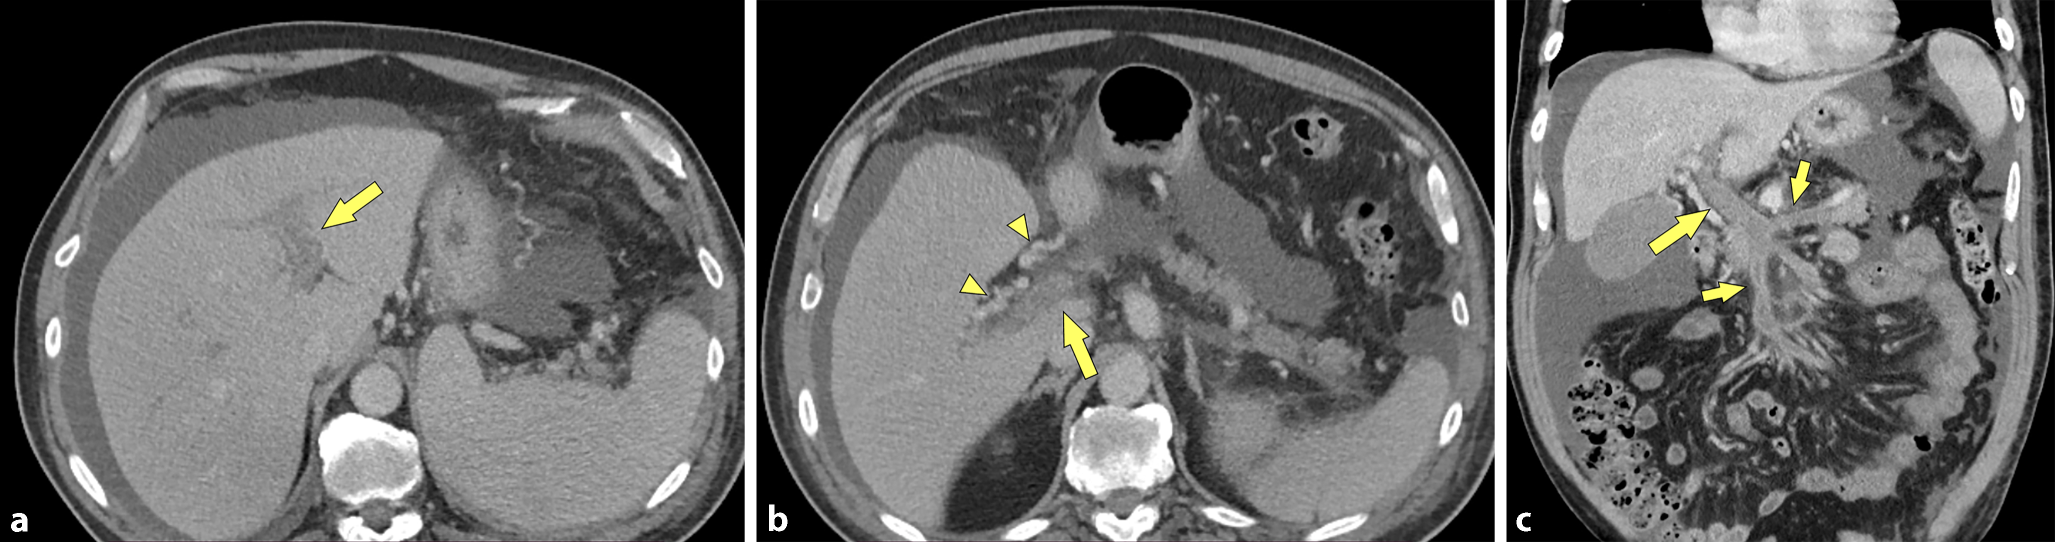

Ein 67 Jahre alter Patient mit bekannter Leberzirrhose (Child-Pugh Score A, MELD 11) wurde aufgrund seit zirka 10 Tagen bestehenden diffusen Bauchschmerzen stationär aufgenommen. Bekannt waren auch dank einer rezenten Gastroskopie das Vorliegen von Ösophagusvarizen und inzipienten Fundusvarizen. Der Patient wurde zur weiteren Abklärung zu einer kontrastmittelverstärkten Multidetektor-CT (MDCT) zugewiesen, welche eine ausgeprägte Thrombose sowohl der intra- und extrahepatischen Pfortader, der V. mesenterica superior und der V. lienalis zeigte (Abb. 1). Überdies zeigte sich aufgrund der ausgedehnten Thrombose eine Splenomegalie und auch Aszites. Aufgrund fehlender Zeichen einer Darmischämie wurde von einer chirurgischen Intervention abgesehen, es wurde stattdessen eine therapeutische Antikoagulation mit niedermolekularem Heparin und in weiterer Folge Apixaban eingeleitet. Die Abklärung hinsichtlich einer zu Grunde liegenden Gerinnungsstörung brachte kein Ergebnis, es fand sich auch keine Neoplasie. Im weiteren Verlauf kam es zum Auftreten von Melaena. In der daraufhin durchgeführten Gastroskopie fand sich kein Hinweis auf eine Blutung. Die MDCT-Verlaufskontrolle zeigte eine ausgeprägte Verdickung der proximalen Jejunumschlingen, mit Zeichen petechialer Einblutungen (Abb. 2). Die Kontrastmittel-MDCT zeigte auch eine Abgangsstenose des Truncus ceoliacus mit poststenotischer fusiformer Ektasie bei Vorliegen eines Ligamentum arcuatum. Allerdings zeigten sich keine Kollateralen zwischen Tr. coel. und A. mes. sup., was eine hämodynamisch signifikante Stenose weitgehend ausschloss. Zum Ausschluss einer paraneoplastischen Mesenterialvenenthrombose wurde nach dem Kontrastmittel-MDCT, der Gastro-Duodenoskopie und der Colonoskopie noch eine MR-Enterographie zwei Wochen später durchgeführt, welche keinen Hinweis auf einen Tumor im Dünndarm ergab, jedoch die Rückbildung des Dünndarmödems zeigte (Abb. 3). Aufgrund der bekannten und nur partiell rekanalisierten Thrombose von Pfortader, V. mes. sup. und V. lienalis zeigte sich auch eine progrediente Splenomegalie. Eine diagnostische Aszitespunktion erbrachte keine weiteren Erkenntnisse. Unter adäquater Schmerztherapie und Anpassung der internistischen Therapie konnte eine deutliche Besserung des Allgemeinzustandes erreicht werden. Die weiterführende laborchemische Abklärung der incipienten Leberzirrhose war unauffällig, sodass eine Leberbiopsie im Rahmen eines Folgeaufenthaltes geplant wurde.

Abb. 2

Die CT-Verlaufskontrolle (nach 6 Tagen) in arterieller (a) und portal-venöser (b) Phase zeigt eine ausgeprägte ödematöse Verdickung der proximalen Jejunumschlingen (offene Pfeile). Man erkennt eine deutliche Hyperdensität der Mukosa im Sinne ausgeprägter petechialer Einblutungen, ursächlich für die Melaena